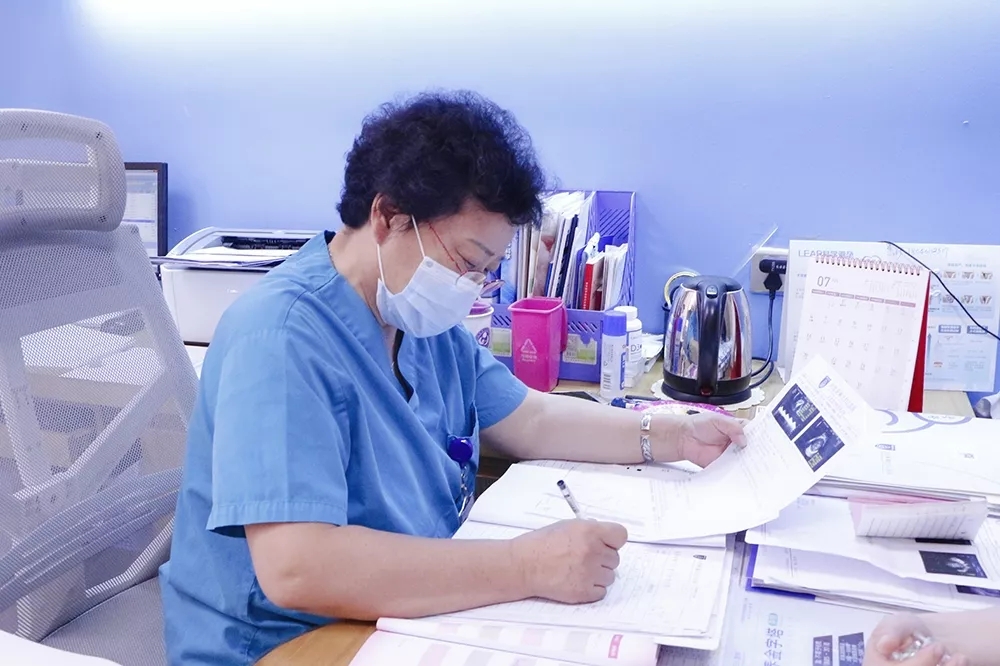

今天,美琳达超声科首席医生杨光

做客小美直播间

一起听听杨光主任是怎么解读的吧~

(图片为非疫情期间拍摄)

(图片为非疫情期间拍摄)

(图片为非疫情期间拍摄)

实力医生领衔团队

美琳达超声科由原大连大学附属中山医院妇产超声科主任、辽宁省超声医学工程学会妇产科委员会副主委,美琳达妇儿医院超声科首席医生杨光,以及原湖北省三甲医院超声科医生,美琳达四维彩超主任陈月芳领衔。他们平均拥有三十余年妇产科超声经验,在系统超声诊断与鉴别方面技术高超,检查严谨细致,行业生涯无一例漏诊、误诊,超声业内享有盛誉,深受广大女性及孕妈信赖和认可。

(图片为非疫情期间拍摄)